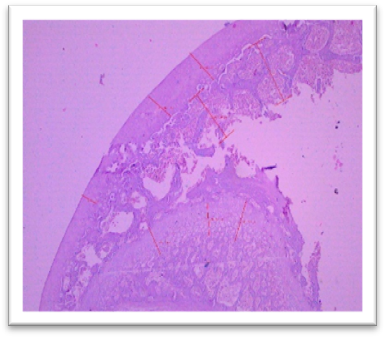

Histomorphometry

At the end of the study, femur bones were dissected and fixed for histological analysis. Group I (Normal) showed normal bone architecture, with well-organized chondrocytes. Group II (Lanthanum Carbonate only) maintained normal bone growth. Group III (Chronic Kidney Disease control) exhibited fibrocartilaginous changes, disorganized collagen, and impaired endochondral ossification, characteristic of Chronic Kidney Dosease. Groups IV (150 mg/kg), V (250 mg/kg), VI (500 mg/kg), and VII (750 mg/kg) demonstrated varying degrees of improvement in bone structure, with the highest dose (Group VII) showing the most significant restoration of normal bone architecture. Histomorphometry of bone: In Group III, designated as positive control for Chronic Kidney Disease, histomorphometric analysis of femur revealed significant fibrocartilaginous changes within the articular cartilage, characterized by an increased fibroblast, loss of chondrocyte organization, and disorganized collagen deposition. Furthermore, the growth plate exhibited a marked increase in the thickness of the hypertrophic zone, suggesting impaired endochondral ossification. Similar findings were observed by Saito et al. (2021) who observed that in Adenine-induced Chronic Kidney Disease, there was a reduction in bone minera density (BMD) throughout the body as well as in the femur Furthermore, micro- computed tomography (micro-CT) analysis revealed a decline in the microstructural integrity of the cortical bone, which contributed to diminished bone strength in both cortical and trabecular regions. Ferrari et al. (2014) reported that the bone microarchitecture in rats subjected to Adenine-induced renal failure exhibited significant alterations, characterized by a reduced trabecular number and an increased trabecular separation. Additionally, the presence of fibrosis was noted in the rats with Adenine-induced renal failure. Ni et al. (2018) performed a histomorphometry analysis and revealing that the bone mineral density (BMD) in the femurs of rats with Chronic Kidney Disease (CKD) was markedly lower than that observed in the control (CTL) group. Additionally, significant bone loss was evident in both cortical and trabecular bone parameters of the femurs.  Lanthanum Carbonate @150mg/kg, 250mg/kg, 500mg/kg and 750 mg/kg, histomorphometric analysis revealed very minimal to nearly absent fibroblast proliferation in the articular cartilage, characterized by the absence of fibroblast- like cells and well-maintained chondrocyte organization. Additionally, the growth plate exhibited moderate proliferation of the hypertrophic zone, indicating significant improvement in endochondral ossification compared to the positive control group (Group III) and lower-dose treatment groups. These findings suggest that the highest dose of Lanthanum Carbonate (750 mg/kg) may provide the most effective therapeutic benefits in mitigating bone-related pathological changes associated with Chronic Kidney Disease Yajima et al. (2018) demonstrated that Lanthanum Carbonate enhanced the mineralization of the periosteal surface, augmented bone mass within the intracortical resorption areas, and improved mineralization on the minimodeling surface at the endocortical region. They concluded that Lanthanum Carbonate has the potential to bolster cortical stability in patients with Chronic Kidney Disease (CKD)..

Fig. 26 Group III femur, showing fibrocartilaginous changes, fibroblasts, loss of chondrocyte organization, and disorganized collagen deposition at articular cartilage. Increased thickness of the hypertrophic zone in the growth plate